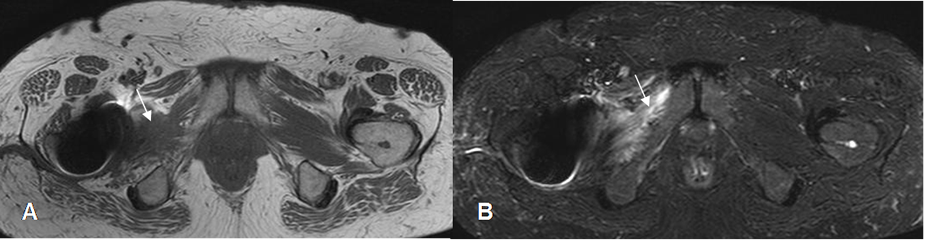

Fig 140. Ruptura parcial.

A: RM axial en T1 y B: RM axial en STIR. Alteración en la señal y configuración del músculo obturador externo, con ruptura de algunas fibras. Existe artefacto, ocasionado por prótesis de cadera.